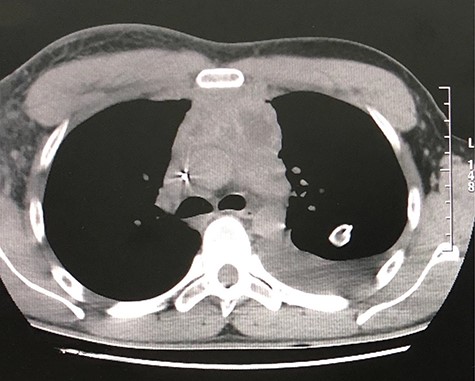

The second case consists of a 47-year-old male from a rural location in Guatemala that presented with malaise, fever, nausea, vomiting and left chest pain, described as oppressive that irradiates toward the neck. The pain got worse while being on supine position. The patient was previously treated with antibiotics and underwent a left thoracostomy due to a chest radiograph that showed a pleural effusion in the lung base (Fig. 3). On chest auscultation and percussion, air entry was reduced and dullness was perceived in the left lung base, respectively. Due to these findings, laboratory tests were ordered. The blood test showed an elevated lactate dehydrogenase at 156 U/L and the pleural fluid analysis showed an elevated lactate dehydrogenase at 1282 U/L, cholesterol level at 66 mg/dl, triglyceride level at 128 mg/dl, presence of Klebsiella pneumoniae and a hematoxylin stain positive for helminth larvae. According to these results, the pleural effusion was classified as an exudate. The high triglyceride level was consistent with a chylous effusion. A chest CT showed left loculated pleural effusion, cardiomegaly, slight pericardial effusion and mediastinal adenomegaly (Fig. 4). The patient presented full recovery after surgical and medical treatment.

CT scan axial view of left pleural effusion, cardiomegaly and pericardial effusion.